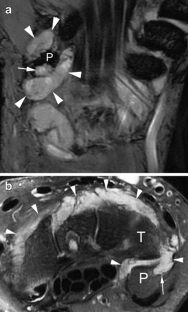

Pisotriquetral joint disorders: an under-recognized cause of ulnar side wrist pain

Pisotriquetral joint disorders are often under-recognized in routine clinical practice. They nevertheless represent a significant cause of ulnar side wrist pain. The aim of this article is to present the main disorders of this joint and discuss the different imaging modalities that can be useful for its assessment.